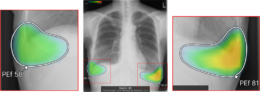

(3)所見名/スコア表示機能

従来のバージョンでは、複数の異常所見を検出した場合、検出された異常所見のうち最も確信度が高い所見のスコアのみを表示しており、各所見のスコアを確認したいという要望があった。新バージョンでは、各検出領域に対応する所見名と確信度を示すスコアを個別に表示できるようになった。これにより、医師は複数の異常所見について詳しい情報をひと目で把握でき、正確な診断を行うことが期待できる。

また、従来のバージョンでは、対象所見が重なった領域においてヒートマップが重なって表示されていた。そのため、異なる所見が混在している部分の識別が難しく、細かな判別や詳細な確認には限界があった。これに対し、新バージョンでは、対象所見が重なった領域についても、各所見ごとに独立した輪郭線を表示できるようになりなった。複数の異常所見が存在する箇所でも、それぞれの所見の範囲を明確に区別できるようになり、より詳細かつ正確な画像診断支援が期待される。